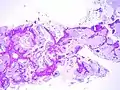

Mucinous BAC

Non-mucinous BAC